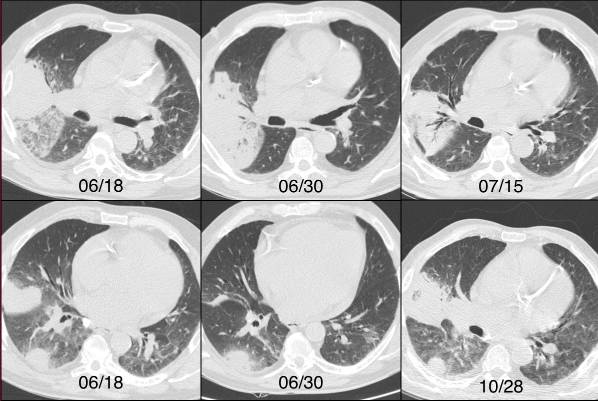

影像学特征包括肺段实变可能是双侧的。可能表现空洞和胸膜增厚。多发结节可能与实变相关。

图1 一例酗酒和营养不良患者右肺慢性实变的进展。半侵袭性曲霉病